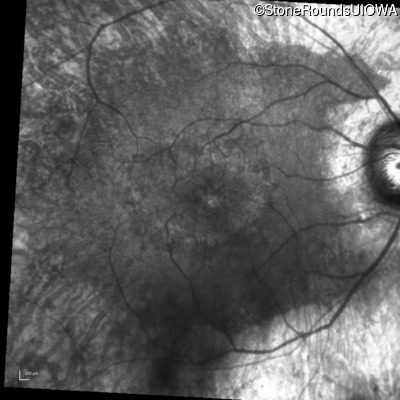

AR Retinitis Pigmentosa (IA1aiii)

Age at visit: 66 years

OD OS